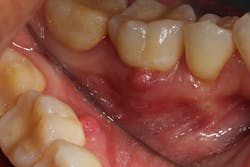

A periapical radiolucency is a hole in the bone formed as a result of inflammation under the root of the tooth as a means of housing the immune system to prevent the bacteria in the root canal from reaching the bone. It can be a precursor to a sinus tract (figure 1), which creates a path for drainage of inflammation into the oral cavity, rather than allowing it to spread through tissue planes.